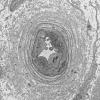

VASCULAR

Hypoxia-Ischemia, fetal-neonatal

White Matter (11)